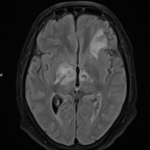

Brian’s journey took a dramatic turn when he returned to the emergency room after Thanksgiving. It was then that medical imaging—through MRI and CT scans—revealed a mass in his sinuses. Initially thought to be squamous cell carcinoma, the mass was later reclassified as small cell neuroendocrine carcinoma, a rare and highly aggressive form of cancer. This revelation highlights the tricky parts of differentiating between various types of cancers, particularly when they occur in less typical locations.

Modern medical imaging has dramatically improved our ability to get into the nitty-gritty of a patient’s physical condition. However, even these advanced techniques can sometimes present confusing bits. In Brian’s case, the initial assumption by some medical personnel and the subsequent detailed analysis underscored how a revisit to one’s diagnosis can be both intimidating and essential.